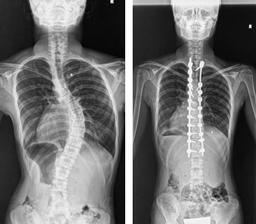

後方矯正固定術

せなかを切開してチタンなどで作られた椎弓根スクリューをせぼねに挿入して、ロッドと呼ばれる金属のバーで固定して、せぼねの矯正と固定を行います。術後に手術部の安静を保つために装具を3-6ヶ月程度着用します。

せなかを切開する場合が多いですが、状態によっては側方経路腰椎椎体間固定術(Lateral Lumbar Interbody Fusion: LIF)や、経皮的椎弓根スクリュー(Percutaneous Pedicle Screw: PPS)をはじめとした体への負担を軽減する手法も取り入れられています。

手術時間は4時間程度で、入院期間はこどもの患者様で2週間程度、大人の患者様では2週間程度で場合によってはリハビリテーション病院へ転院をして頂き、さらにリハビリテーションを行います。

-

こどもの特発性側弯症に対する後方矯正固定術 -

大人の側弯症に対する後方矯正固定術